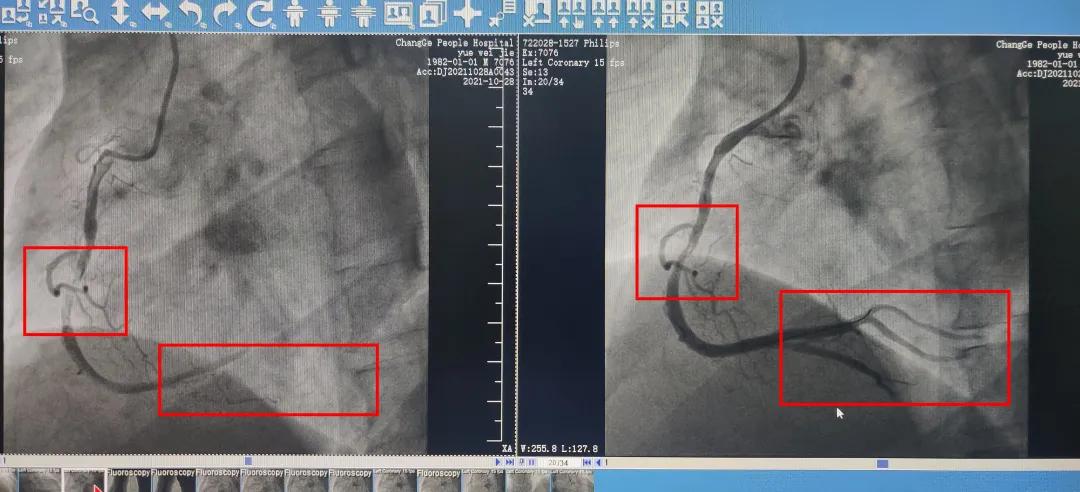

图为岳先生手术前后的血管造影图。

据介绍,这位病人年仅39岁,同样因为突发的急性心肌梗死入院手术。当天上午10点30分,这位同样姓岳病人被送到市人民医院大门口,经过35分钟救治成功脱离危险。

“这位岳先生的情况更具有代表性。这个病人的家距离城区较远,家属是拨打120求救的,在被送到市第二人民医院确诊后,那里的医生已经为他进行了前期治疗,稳住了凶险的病情,随后才被送到我们医院进行介入手术。类似的紧急抢救在救治急性心肌梗死这种急性疾病时候非常重要。”尚伟民说,“另外,这位病人还不到40岁。根据我们医院的记录显示,急性心肌梗死近年来也确实有年轻化的趋势,有必要引起全社会的进一步重视。”